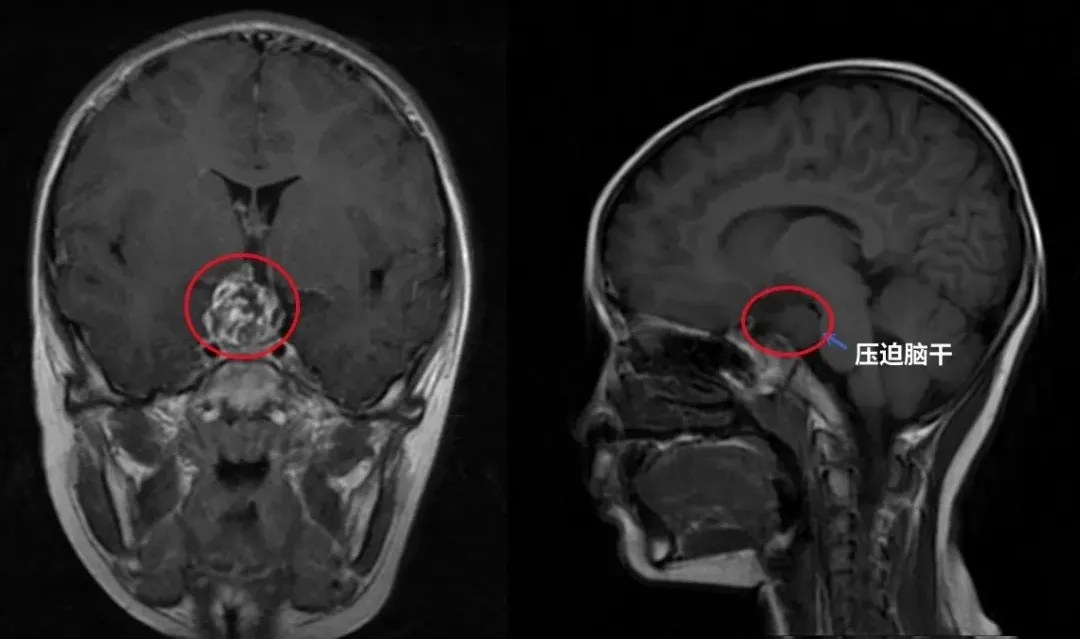

巴教授为他示范手术,术前术后影像对比